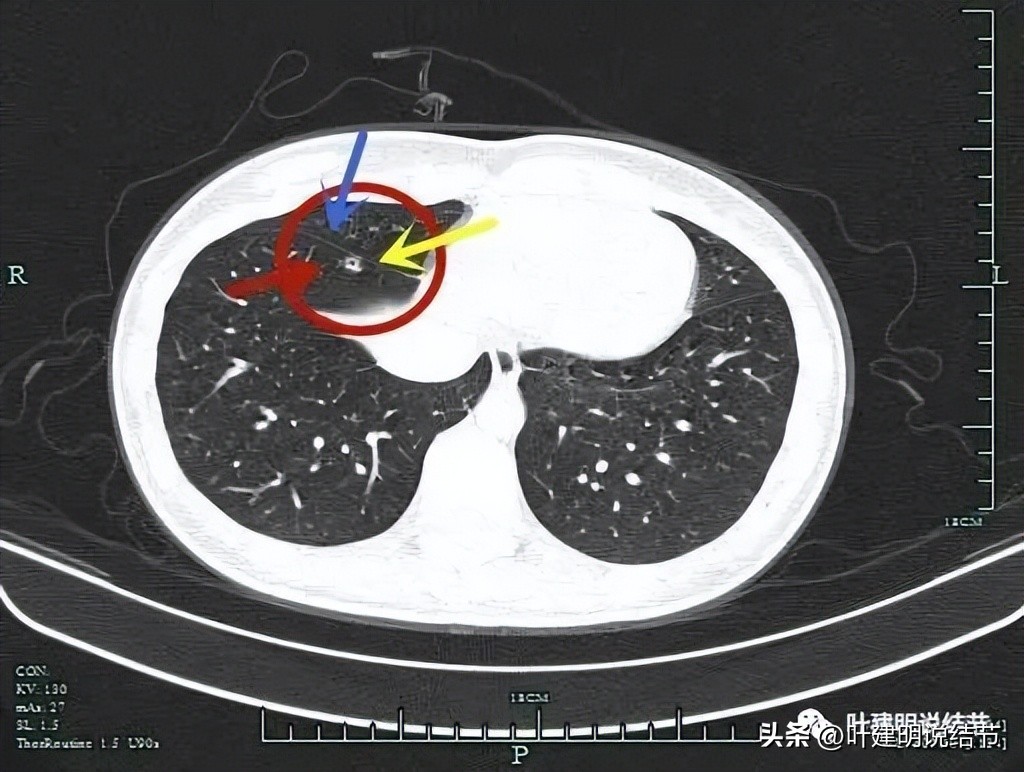

影像特点:

左上叶实性占位,边缘有磨玻璃成分,有较为典型的血管征、分叶征、毛刺征以及支气管截断征,首先考虑恶性肿瘤。相关其他检查无明显远处转移征象。